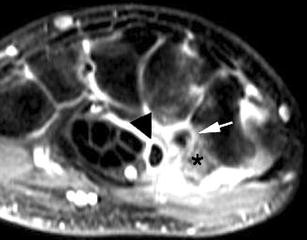

Results

Five of the patients showed evidence of triscaphe osteoarthritis. One of the patients showed synovitis and reactive marrow edema at the triscaphe joint without more specific findings of osteoarthritis. Five patients showed evidence of FCR tenosynovitis. Partial-thickness tears were noted in three patients. Two patients showed complete discontinuity of the FCR; one of them had undergone prior tendon harvesting for interposition arthroplasty after trapezectomy. One patient showed a ganglion cyst in connection to the FCR tendon sheath.

The FCR tendon courses over the volar surfaces of the scaphoid and trapezium in a separate fibro-osseous tunnel. This anatomical and functional relationship explains the coexistence of FCR tendinopathy and STT arthritis demonstrated by MR imaging.